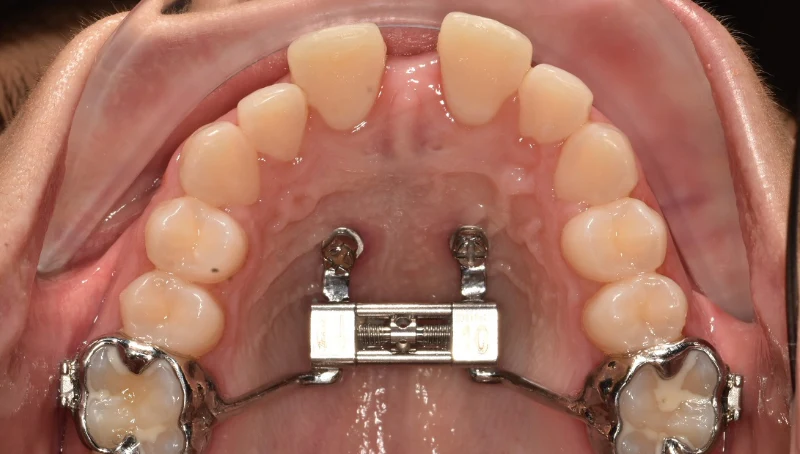

1754917002022.jpg

Че будет завтра со мной?